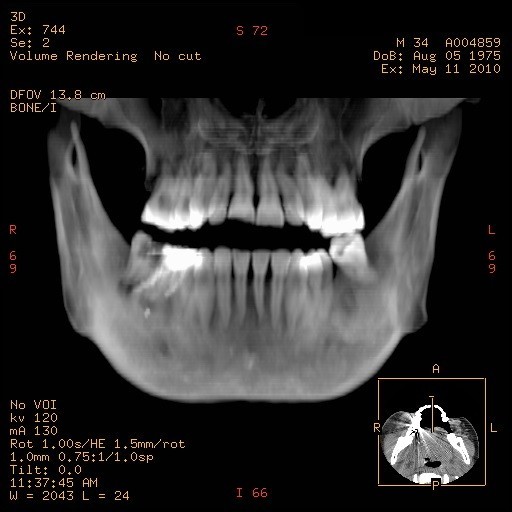

Es una técnica que permite una óptima planeación preoperatoria de la colocación de un implante dental.

Los implantes óseo-integrados se han convertido en una forma aceptada de reemplazo dental permanente. Un importante avance en la evaluación preoperatoria de los candidatos para colocación de implantes es el desarrollo de un software para escanografia que es capaz de generar imágenes panorámicas y axiales del maxilar superior y de la mandíbula. Estas imágenes permiten al Odontólogo Implantólogo realizar varias medidas para determinar si el sitio es adecuado para la colocación de un implante.

Incluye la altura, ancho y angulación del reborde alveolar; calidad del hueso en el sitio del implante; relación del sitio del implante con las estructuras adyacentes como son el reborde alveolar, canal mandibular y foramen mentoneano en la mandíbula y el reborde alveolar, la fosa nasal, el seno maxilar y el ducto nasopalatino en el maxilar superior. La medición por escanografía es un método muy exacto de planeación permitiendo así una adecuada óseo integración del implante que ayuda al éxito del mismo.